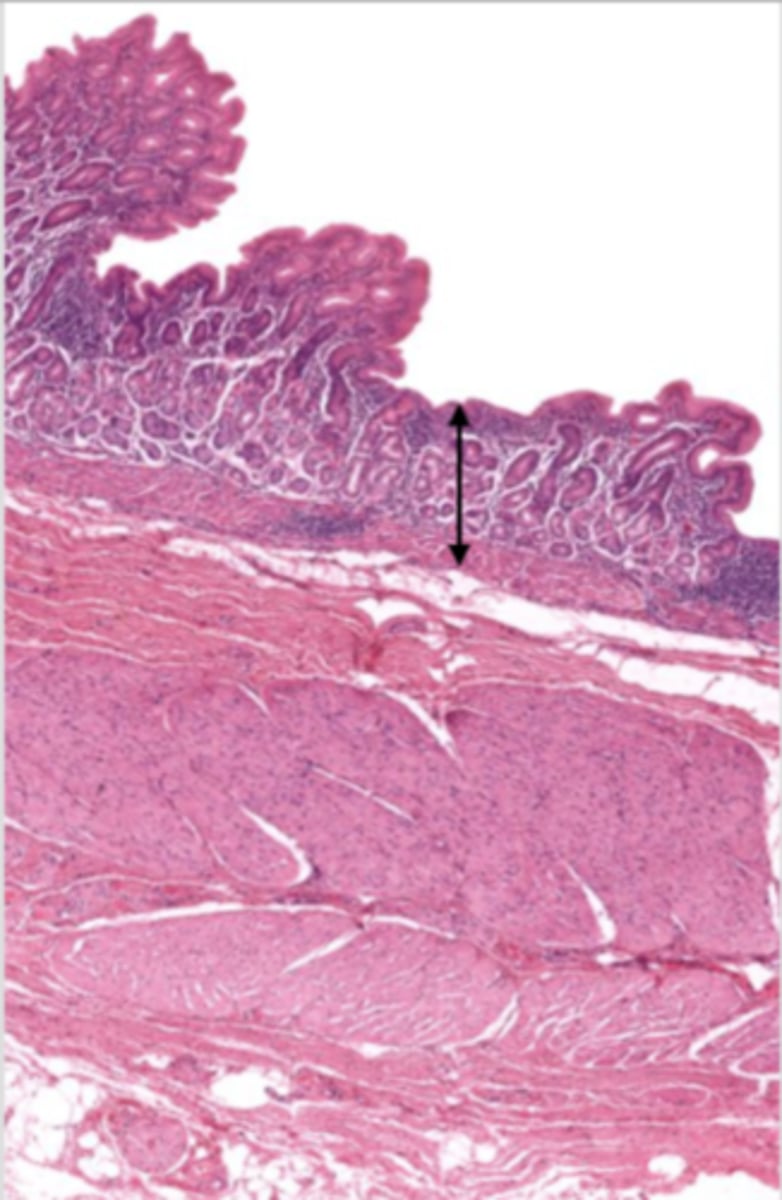

cardiac stomach (histology)

simple columnar epithelium

what kind of epithelium lines the mucosa of the cardiac stomach?

gastric pit (cardiac stomach)

lumen (cardiac stomach)

mucosa (cardiac stomach)

mucosal epithelium (cardiac stomach)

lamina propria (cardiac stomach)

muscularis mucosa (cardiac stomach)

submucosa (cardiac stomach)

contains glands and blood supply

muscularis externa (cardiac stomach)

serosa/adventitia (cardiac stomach)